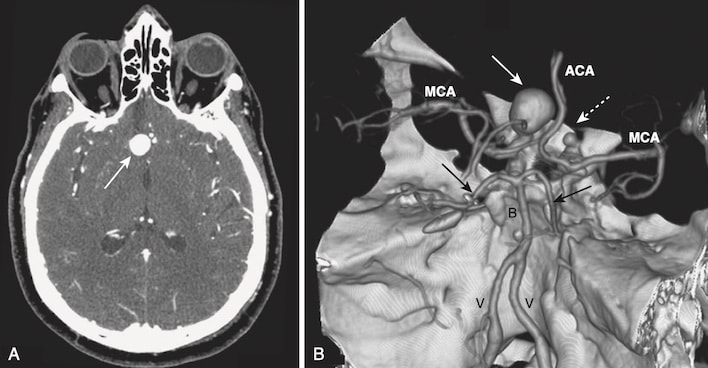

VỠ PHÌNH MẠCH (RUPTURED ANEURYSMS)

- Phình mạch hệ thần kinh trung ương thường gặp nhất là phình động mạch hình túi (berry aneurysm), phát triển từ sự suy yếu bẩm sinh ở thành động mạch, thường là ở các vị trí phân nhánh mạch máu trong vòng Willis ở đáy não. Nó có thể mang tính chất gia đình (khoảng 10% trường hợp) hoặc liên quan đến các bệnh mô liên kết.

- Tăng huyết áp và lão hóa đóng một vai trò trong sự phát triển của phình động mạch. Những túi phình lớn hơn thường chảy máu hơn những túi phình nhỏ hơn.

- Mục đích là phát hiện và điều trị chứng phình động mạch trước khi nó bị chảy máu lớn. Trong một số nghiên cứu, kích thước được xem là quan trọng với vỡ phình mạch là 10 mm.

- Khi phình mạch bị vỡ, máu thường đi vào khoang dưới nhện.

- Vỡ túi phình là nguyên nhân không do chấn thương phổ biến nhất của xuất huyết dưới nhện (80%) nhưng không phải là nguyên nhân duy nhất, bởi vì chấn thương, dị dạng động tĩnh mạch (AVM), hoặc chảy máu trong nhu mô cũng có thể gây xuất huyết dưới nhện.

- Ngày nay, hầu hết các phình động mạch được phát hiện bằng chụp mạch CT hoặc chụp mạch MR.

- Chụp mạch CT được thực hiện bằng cách sử dụng một kim phun điện để truyền nhanh (bolus) thuốc cản quang i-ốt vào tĩnh mạch, một máy quét CT có khả năng thu thập dữ liệu nhanh chóng và các thuật toán máy tính đặc biệt và kỹ thuật xử lý hậu kỳ có thể làm nổi bật các mạch máu và nếu muốn, hiển thị chúng theo ba chiều (Hình 20).

- Nhận biết xuất huyết dưới nhện (do vỡ phình động mạch) (Hình 21)

- Trên CT, chảy máu cấp tính tăng đậm độ và có thể được nhìn thấy trong các rãnh não và bể đáy (xem Hình 21, A và 21, B).

- Vùng liềm có thể trở nên tăng đậm, rộng ra và có bờ bất thường (xem Hình 21, C).

- Nói chung, nơi có tập trung máu nhiều nhất có thể là nơi có khả năng vỡ phình động mạch cao nhất.